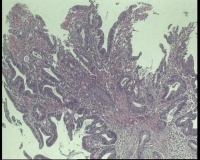

急!请老师帮忙看看,单位同事肠镜病理

进镜达横结肠近肝曲,见不规则增生性肿物,环周生长,表面充血糜烂,触之易出血,肠腔狭窄,镜身无法通过

肠镜活检4块

镜下腺体异型小,纤维间质反应,能直接报结肠腺癌吗?

可一类报告报:管状绒毛状腺癌

高-中分化腺癌。